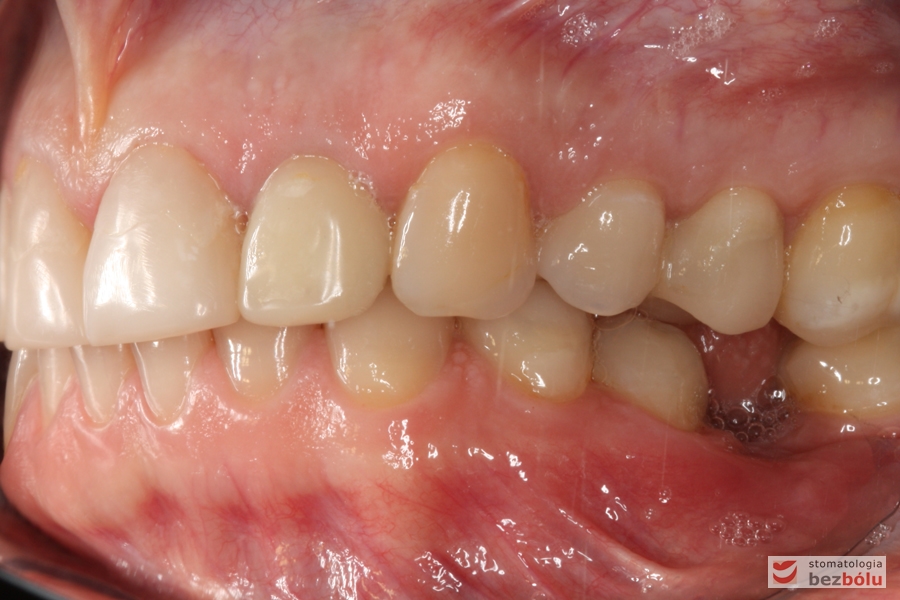

Zęby w zgryzie - strona prawa, II klasa kłowa i Angle'a, mezjalna inklinacja kła

Zęby w zgryzie – strona prawa, II klasa kłowa i Angle’a, mezjalna inklinacja kła